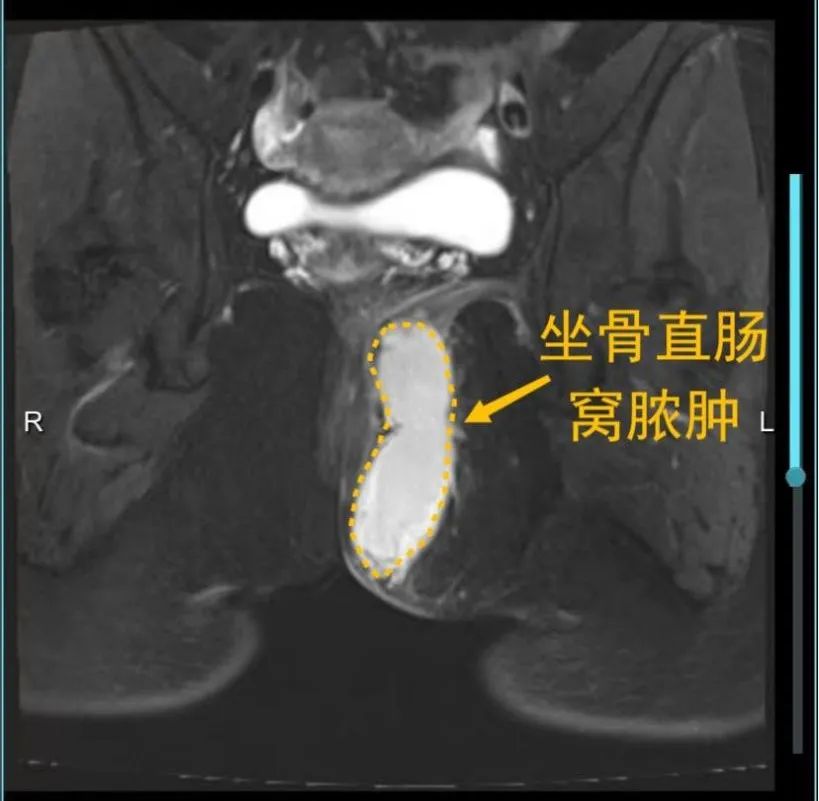

肛周脓肿,又称肛管直肠周围脓肿,中医称为“肛痈”。指肛管和直肠周围软组织内或其周围间隙内发生急性化脓性感染疾病,其症状是肛周持续剧烈疼痛,红肿,并伴有发热,恶寒等表现,其特点是自行破溃,或在手术切开引流后常形成肛瘘。